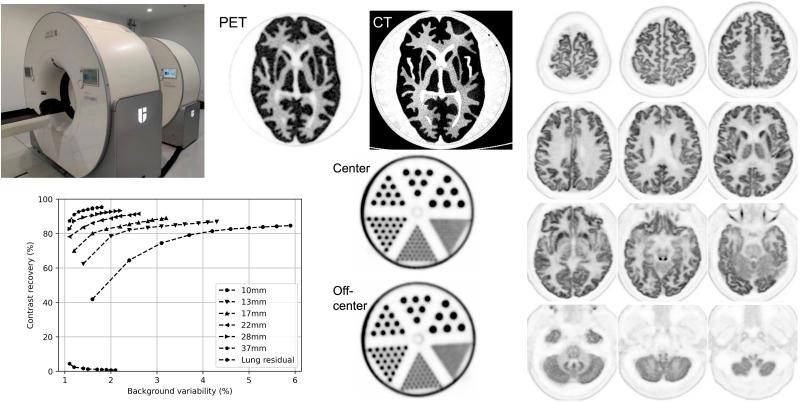

The collaboration of Yale, the University of California, Davis, and United Imaging Healthcare has successfully developed the NeuroEXPLORER, a dedicated human brain PET imager with high spatial resolution, high sensitivity, and a built-in 3-dimensional camera for markerless continuous motion tracking. It has high depth-of-interaction and time-of-flight resolutions, along with a 52.4-cm transverse field of view (FOV) and an extended axial FOV (49.5 cm) to enhance sensitivity. Here, we present the physical characterization, performance evaluation, and first human images of the NeuroEXPLORER. Measurements of spatial resolution, sensitivity, count rate performance, energy and timing resolution, and image quality were performed adhering to the National Electrical Manufacturers Association (NEMA) NU 2-2018 standard. The system's performance was demonstrated through imaging studies of the Hoffman 3-dimensional brain phantom and the mini-Derenzo phantom. Initial F-FDG images from a healthy volunteer are presented. With filtered backprojection reconstruction, the radial and tangential spatial resolutions (full width at half maximum) averaged 1.64, 2.06, and 2.51 mm, with axial resolutions of 2.73, 2.89, and 2.93 mm for radial offsets of 1, 10, and 20 cm, respectively. The average time-of-flight resolution was 236 ps, and the energy resolution was 10.5%. NEMA sensitivities were 46.0 and 47.6 kcps/MBq at the center and 10-cm offset, respectively. A sensitivity of 11.8% was achieved at the FOV center. The peak noise-equivalent count rate was 1.31 Mcps at 58.0 kBq/mL, and the scatter fraction at 5.3 kBq/mL was 36.5%. The maximum count rate error at the peak noise-equivalent count rate was less than 5%. At 3 iterations, the NEMA image-quality contrast recovery coefficients varied from 74.5% (10-mm sphere) to 92.6% (37-mm sphere), and background variability ranged from 3.1% to 1.4% at a contrast of 4.0:1. An example human brain F-FDG image exhibited very high resolution, capturing intricate details in the cortex and subcortical structures. The NeuroEXPLORER offers high sensitivity and high spatial resolution. With its long axial length, it also enables high-quality spinal cord imaging and image-derived input functions from the carotid arteries. These performance enhancements will substantially broaden the range of human brain PET paradigms, protocols, and thereby clinical research applications.

耶鲁大学、加利福尼亚大学戴维斯分校与联影医疗合作,成功研发出NeuroEXPLORER,这是一款专门用于人类大脑的正电子发射断层显像(PET)仪,具有高空间分辨率、高灵敏度,并内置三维相机用于无标记连续运动追踪。它具有高相互作用深度和飞行时间分辨率,以及52.4厘米的横向视野(FOV)和扩展的轴向视野(49.5厘米)以提高灵敏度。在此,我们展示NeuroEXPLORER的物理特性、性能评估及首批人体图像。按照美国国家电气制造商协会(NEMA)NU 2 - 2018标准,对空间分辨率、灵敏度、计数率性能、能量和时间分辨率以及图像质量进行了测量。通过对霍夫曼三维脑模体和迷你德伦佐模体的成像研究展示了该系统的性能。展示了来自一名健康志愿者的初始F - FDG图像。采用滤波反投影重建,对于径向偏移1厘米、10厘米和20厘米,径向和切向空间分辨率(半高宽)平均分别为1.64毫米、2.06毫米和2.51毫米,轴向分辨率分别为2.73毫米、2.89毫米和2.93毫米。平均飞行时间分辨率为236皮秒,能量分辨率为10.5%。NEMA灵敏度在中心处为46.0千计数每秒每兆贝可,在10厘米偏移处为47.6千计数每秒每兆贝可。在视野中心实现了11.8%的灵敏度。在58.0千贝可/毫升时,峰值噪声等效计数率为1.31兆计数每秒,在5.3千贝可/毫升时散射分数为36.5%。在峰值噪声等效计数率下的最大计数率误差小于5%。在3次迭代时,NEMA图像质量对比恢复系数在4.0:1的对比度下,从74.5%(10毫米球体)到92.6%(37毫米球体)不等,背景变化范围从3.1%到1.4%。一张人脑F - FDG图像示例展示出非常高的分辨率,捕捉到了皮质和皮质下结构的复杂细节。NeuroEXPLORER具有高灵敏度和高空间分辨率。凭借其长轴向长度,它还能够实现高质量的脊髓成像以及来自颈动脉的图像衍生输入函数。这些性能提升将极大地拓宽人类大脑PET范式、方案以及临床研究应用的范围。